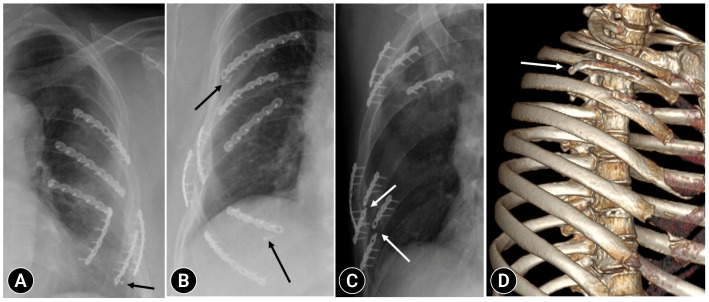

Results: During the study period, 728 patients underwent SSRF, of whom 80 (10.9%) were diagnosed with HF. The mean age of HF patients was 56.5±13.6 years, and 66 (82.5%) were men. There were 59 cases (73.8%) of screw loosening, 21 (26.3%) of plate breakage, 17 (21.3%) of screw migration, and seven (8.8%) of plate dislocation. Nine patients (11.3%) experienced wound infection, and 35 patients (43.8%) experienced chronic pain. A total of 21 patients (26.3%) underwent reoperation for plate removal. The patients in the reoperation group were significantly younger, had fewer fractures and plates, underwent costal fixation, and had a longer follow-up. There were no significant differences in subjective chest symptoms or lung capacity.

Conclusions: HF after SSRF occurred in 10.9% of the cases, and screw loosening was the most common. Further longitudinal studies are needed to identify risk factors for SSRF failure.